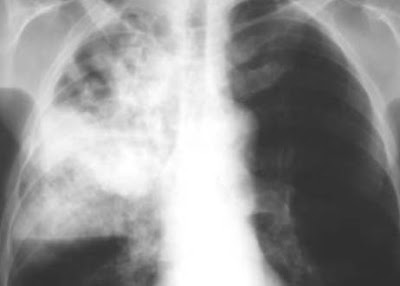

El pasado sábado 3 de Agosto en el auditorio del piso 6C de Medicina Interna se realizó la actividad académica a cargo del residente de segundo año de la especialidad de Medicina Interna Jesús De la Jara Cordero que versó sobre "Neumonía adquirida en la Comunidad"

Sobre Neumonía adquirida en la comunidad existen guías de diagnóstico y manejo, la del IDSA del 2007, la de la BTS del 2009 y de la Sociedad Peruana de Enfermedades Infecciosas y Tropicales también del 2009. Es de utilidad las escalas, sobre todo la CBR-65 para poder hacer una clasificación de pronóstico y manejo, para pasar luego a la terapia empírica establecida según la región y la susceptibilidad de los gérmenes.